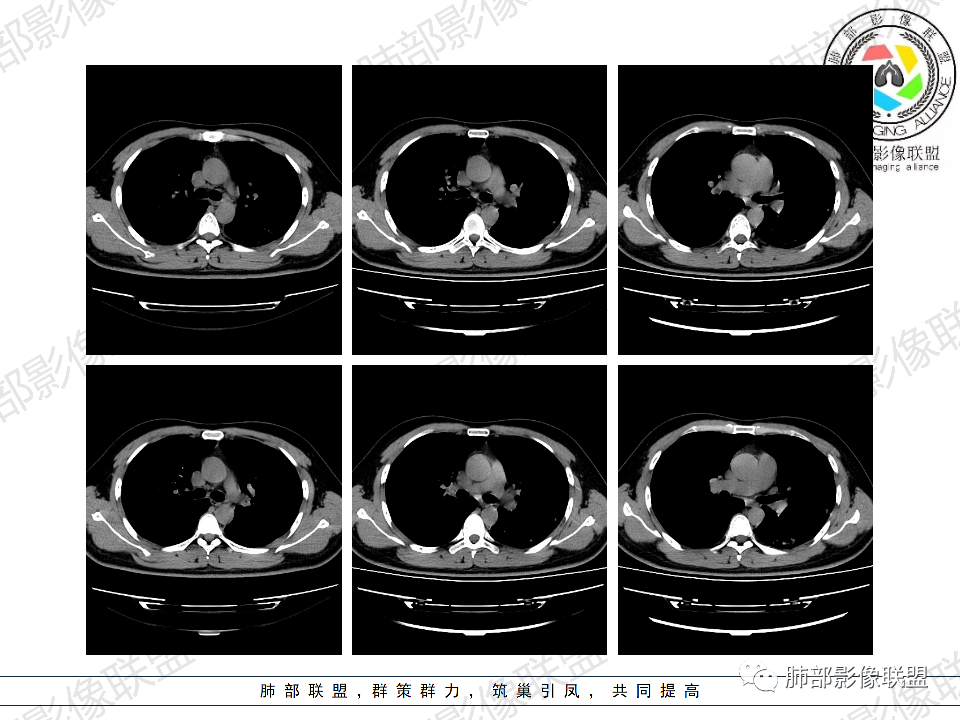

年轻男性,有HIV病史,免疫力缺陷病史,CD4明显减低,左肺胸膜下多发大小不等结节影,部分侧向融合,平行于胸膜,周围伴有模糊的GGO,部分结节与血管相连,血管束增粗,考虑隐球菌,建议查隐球菌荚膜实验,脑脊液隐球菌荚膜,鉴别:CMV(局限性比较少见)

年轻人,男性,HIV阳性,双肺多发斑片状,结节状阴影,以胸膜下分布为主,病灶与支气管血管束垂直生长,周围可见磨玻璃影,考虑肉芽肿病变,隐球菌感染可能性大,鉴别GPA,胞子菌肺炎。

左肺多发大小不等结节影,部分融合,胸膜下分布为主,平行于胸膜,周围伴有磨玻璃晕,考虑隐球菌,鉴别:PJP

年轻男性,HIV阳性,胸闷喘憋,双肺胸膜下多发斑片结节影,周围伴晕,部分融合,白细胞低,CD4明显减低,考虑机会性感染性病变,隐球>PCP>结核

青年男性,HIV阳性,白细胞及淋巴细胞显著降低,CRP增高,胸闷气喘一周,影像为双肺胸膜下平行于胸膜分布的多发大小不等结节伴晕,单从影像上看,隐球是要首先考虑,但是不好解释临床症状。需要鉴别:1、曲霉所致IPA,临床有粒缺基础,胸闷一周要考虑,但影像不是典型的血道或气道分布又存疑,2、马尼,CD4低,HIV基础,要考虑,但是否有旅广史?另外纵隔淋巴结无肿大,肝脾不肿大,可能稍小。3、PCP,HIV基础,CD4低,胸闷气喘要考虑,影像分布不典型。4、腺病毒或EB病毒感染,HIV基础,影像改变要考虑,但是发病无发热,存疑。5、结核,临床与影像均不典型。可能小。综上,隐球>曲霉>PCP>马尼>病毒感染。下一步,查隐球荚膜抗原,NGS找病原体。

5、分布:病灶分布多位于胸膜下,可紧贴胸膜,也可与胸膜邻近,病灶长轴与胸膜平行。(划重点,分布特点非常重要)

10、“葫芦兄弟”:邻近胸膜多发结节,形态密度类似,可簇状分布,较少多形性,没有新旧不等。